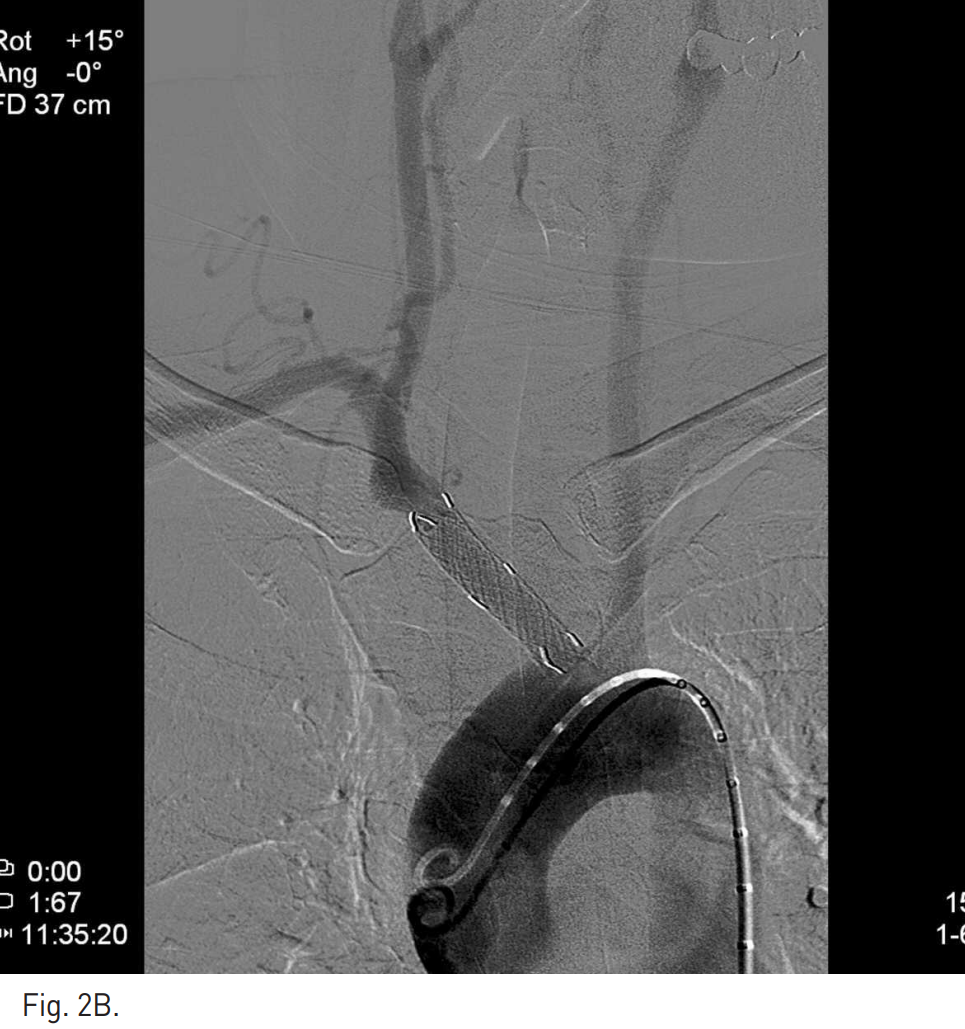

Fig. 2

B. On arch aortogram following deployment of the covered stent, the lesion has been successfully excluded and there is no abnormal finding of supra-aortic arteries.